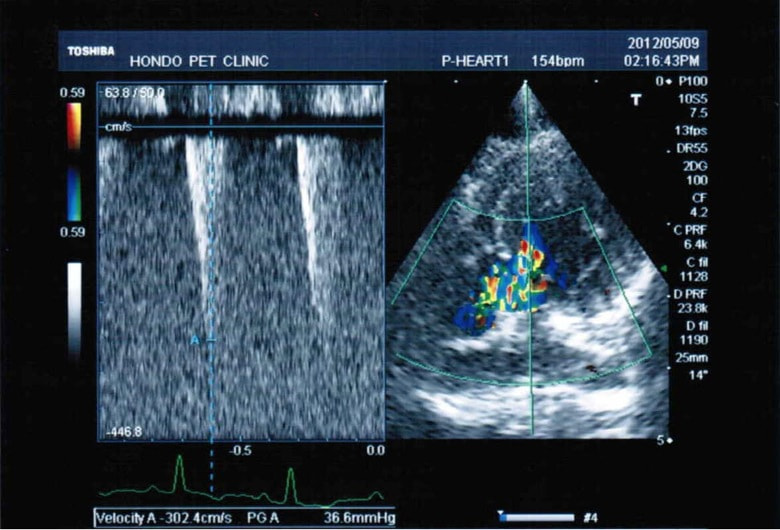

C:超音波写真 僧帽弁逆流と左室流出路狭窄

D:超音波写真 狭窄部の異常血流速度の測定

1年ほど前より左側胸壁からLevine 3/6の心雑音が聴取されていた。雑音の精査のため、心エコー検査を行ったところ、左室流出路の狭窄を伴う肥大型心筋症(閉塞型肥大型心筋症)と判明した。心室の拡張性を上げるため、βブロッカーであるカルベジロールを用いた治療を行っている。肥大型心筋症は犬の心疾患のように、心拡大を認めないことも多く、レントゲン写真のみで心疾患の有無を判断する事が出来ない。また、閉塞を伴わない肥大型心筋症と異なり、閉塞型の本疾患の治療に対し、Caチャネルブロッカーは推奨されない。